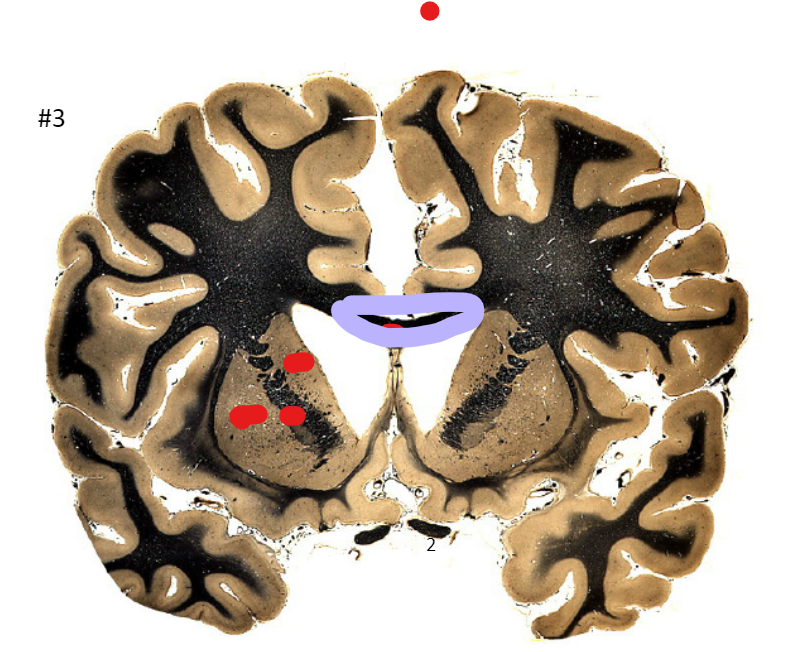

5

Q

what is the circled area (#3)?

A

the corpus callosum

6

the caudate nucleus

7

the internal capsule

8

the putamen

9

the optic nerve